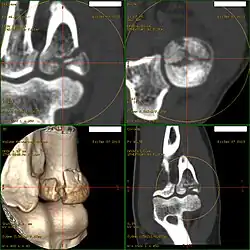

Die Bestätigung liefern Röntgenaufnahmen des Ellenbogens. Allerdings können nicht verschobene Brüche in den Standardaufnahmen leicht übersehen werden. Hilfreich ist hierbei häufig das so genannte Fettpolsterzeichen, welches indirekt einen Gelenkerguss anzeigt. Bei unklarer Situation können zusätzlich zwei 45°-Schrägaufnahmen, eine Computertomographie oder eine Magnetresonanztomographie durchgeführt werden. Letztere sind auch geeignet, begleitende Knochenbrüche etwa des benachbarten Teils des Oberarmknochens (des Capitulum humeri) oder der ellenbogennahen Elle (des Processus coronoideus) darzustellen.